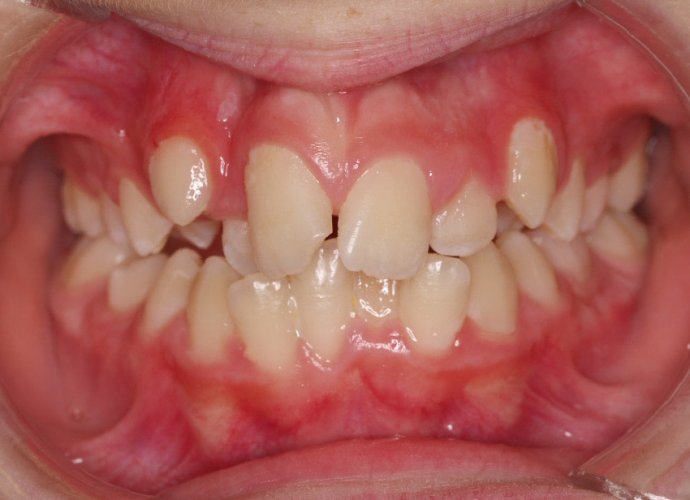

El paciente A.J. de 11 años, acude a nuestra consulta con apiñamiento maxilar importante. El canino lateral (12) está en mordida cruzada. Presenta una Clase II molar y canina, y la línea media está desviada. Se realizó un tratamiento con brackets autoligables metálicos de smartclip 022. La duración del tratamiento fue de 22 meses.

El paciente actualmente ha terminado el tratamiento con brackets y lleva una contención fija de 2-2 en maxilar y 3-3 en mandibular; para complementar también lleva una férula ESSIX durante la noche.

INICIO FINAL